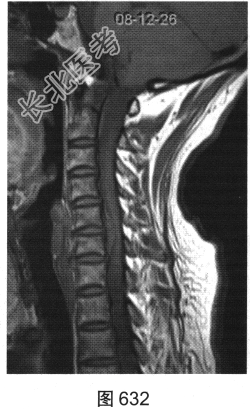

- [材料题] 患者女性,49岁,颈部胀痛伴双手麻木3天。MRI检查见图632~图637。

- 多项选择题1.患者MRI图片有哪些阳性征象( )

A、同水平硬膜囊及脊髓明显受压

B、病变与硬膜夹角为钝角

C、病变呈环形强化,中心未见明显强化

D、病变在髓外硬膜下

E、病变跨越右侧椎间孔,呈哑铃状改变

F、C

水平硬膜外梭形软组织信号